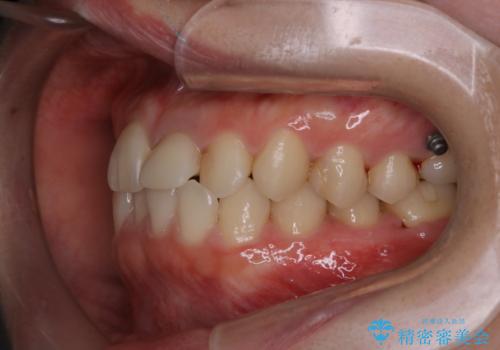

インビザラインのアタッチメントをつける前にPMTC

- インビザラインでの矯正治療中で、アタッチメントの設定前にきれな状態にしたいとのことでした。PMTC30分コースを行いました。

マウスピース矯正インビザライン治療では、歯の表面にアタッチメントという突起を設定します。(アタッチメントは歯の動きを効率的に移動するためのものです)

アタッチメントの設定時に、プラークや歯石・着色がついていると精密に付かないことや、外れやすくなることがあります。

PMTCを行い、専門的な機械でしっかりと汚れを除去してからアタッチメントの設定をすることがおススメです。